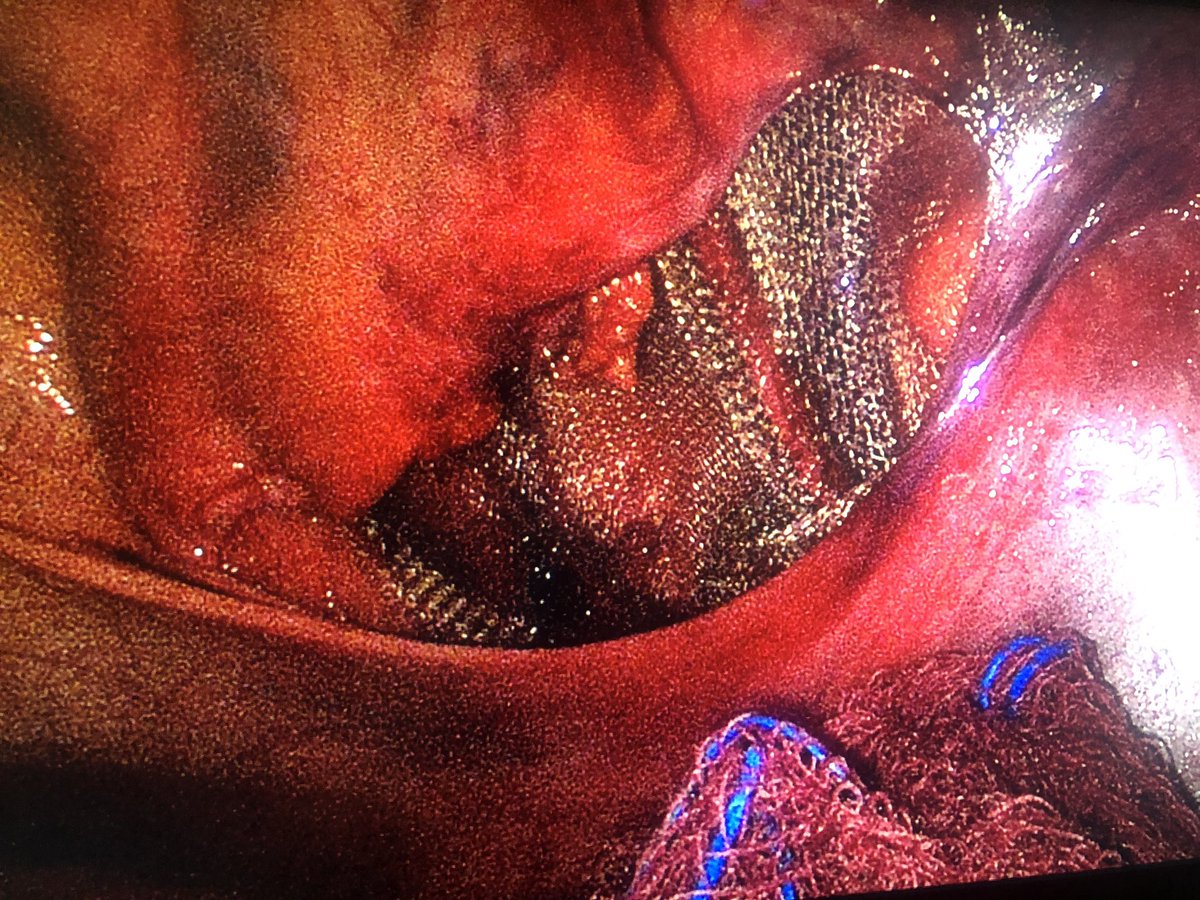

Se siente bien bonito ver a mis bebesaurios en acción 🔪

Montse Gp tweet mediaMontse Gp tweet media

@montse_gp55 Bien! Muy bien! Solo falta afinar la ergonomía! Poco a poco